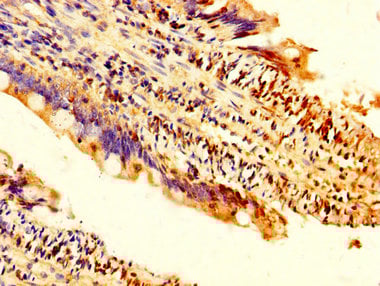

IHC (Immunohiostchemistry)

(Formalin-fixed and paraffin-embedded human cancer tissue reacted with the primary antibody, which was peroxidase-conjugated to the secondary antibody, followed by DAB staining. This data demonstrates the use of this antibody for immunohistochemistry; clinical relevance has not been evaluated. BC = breast carcinoma; HC = hepatocarcinoma.)